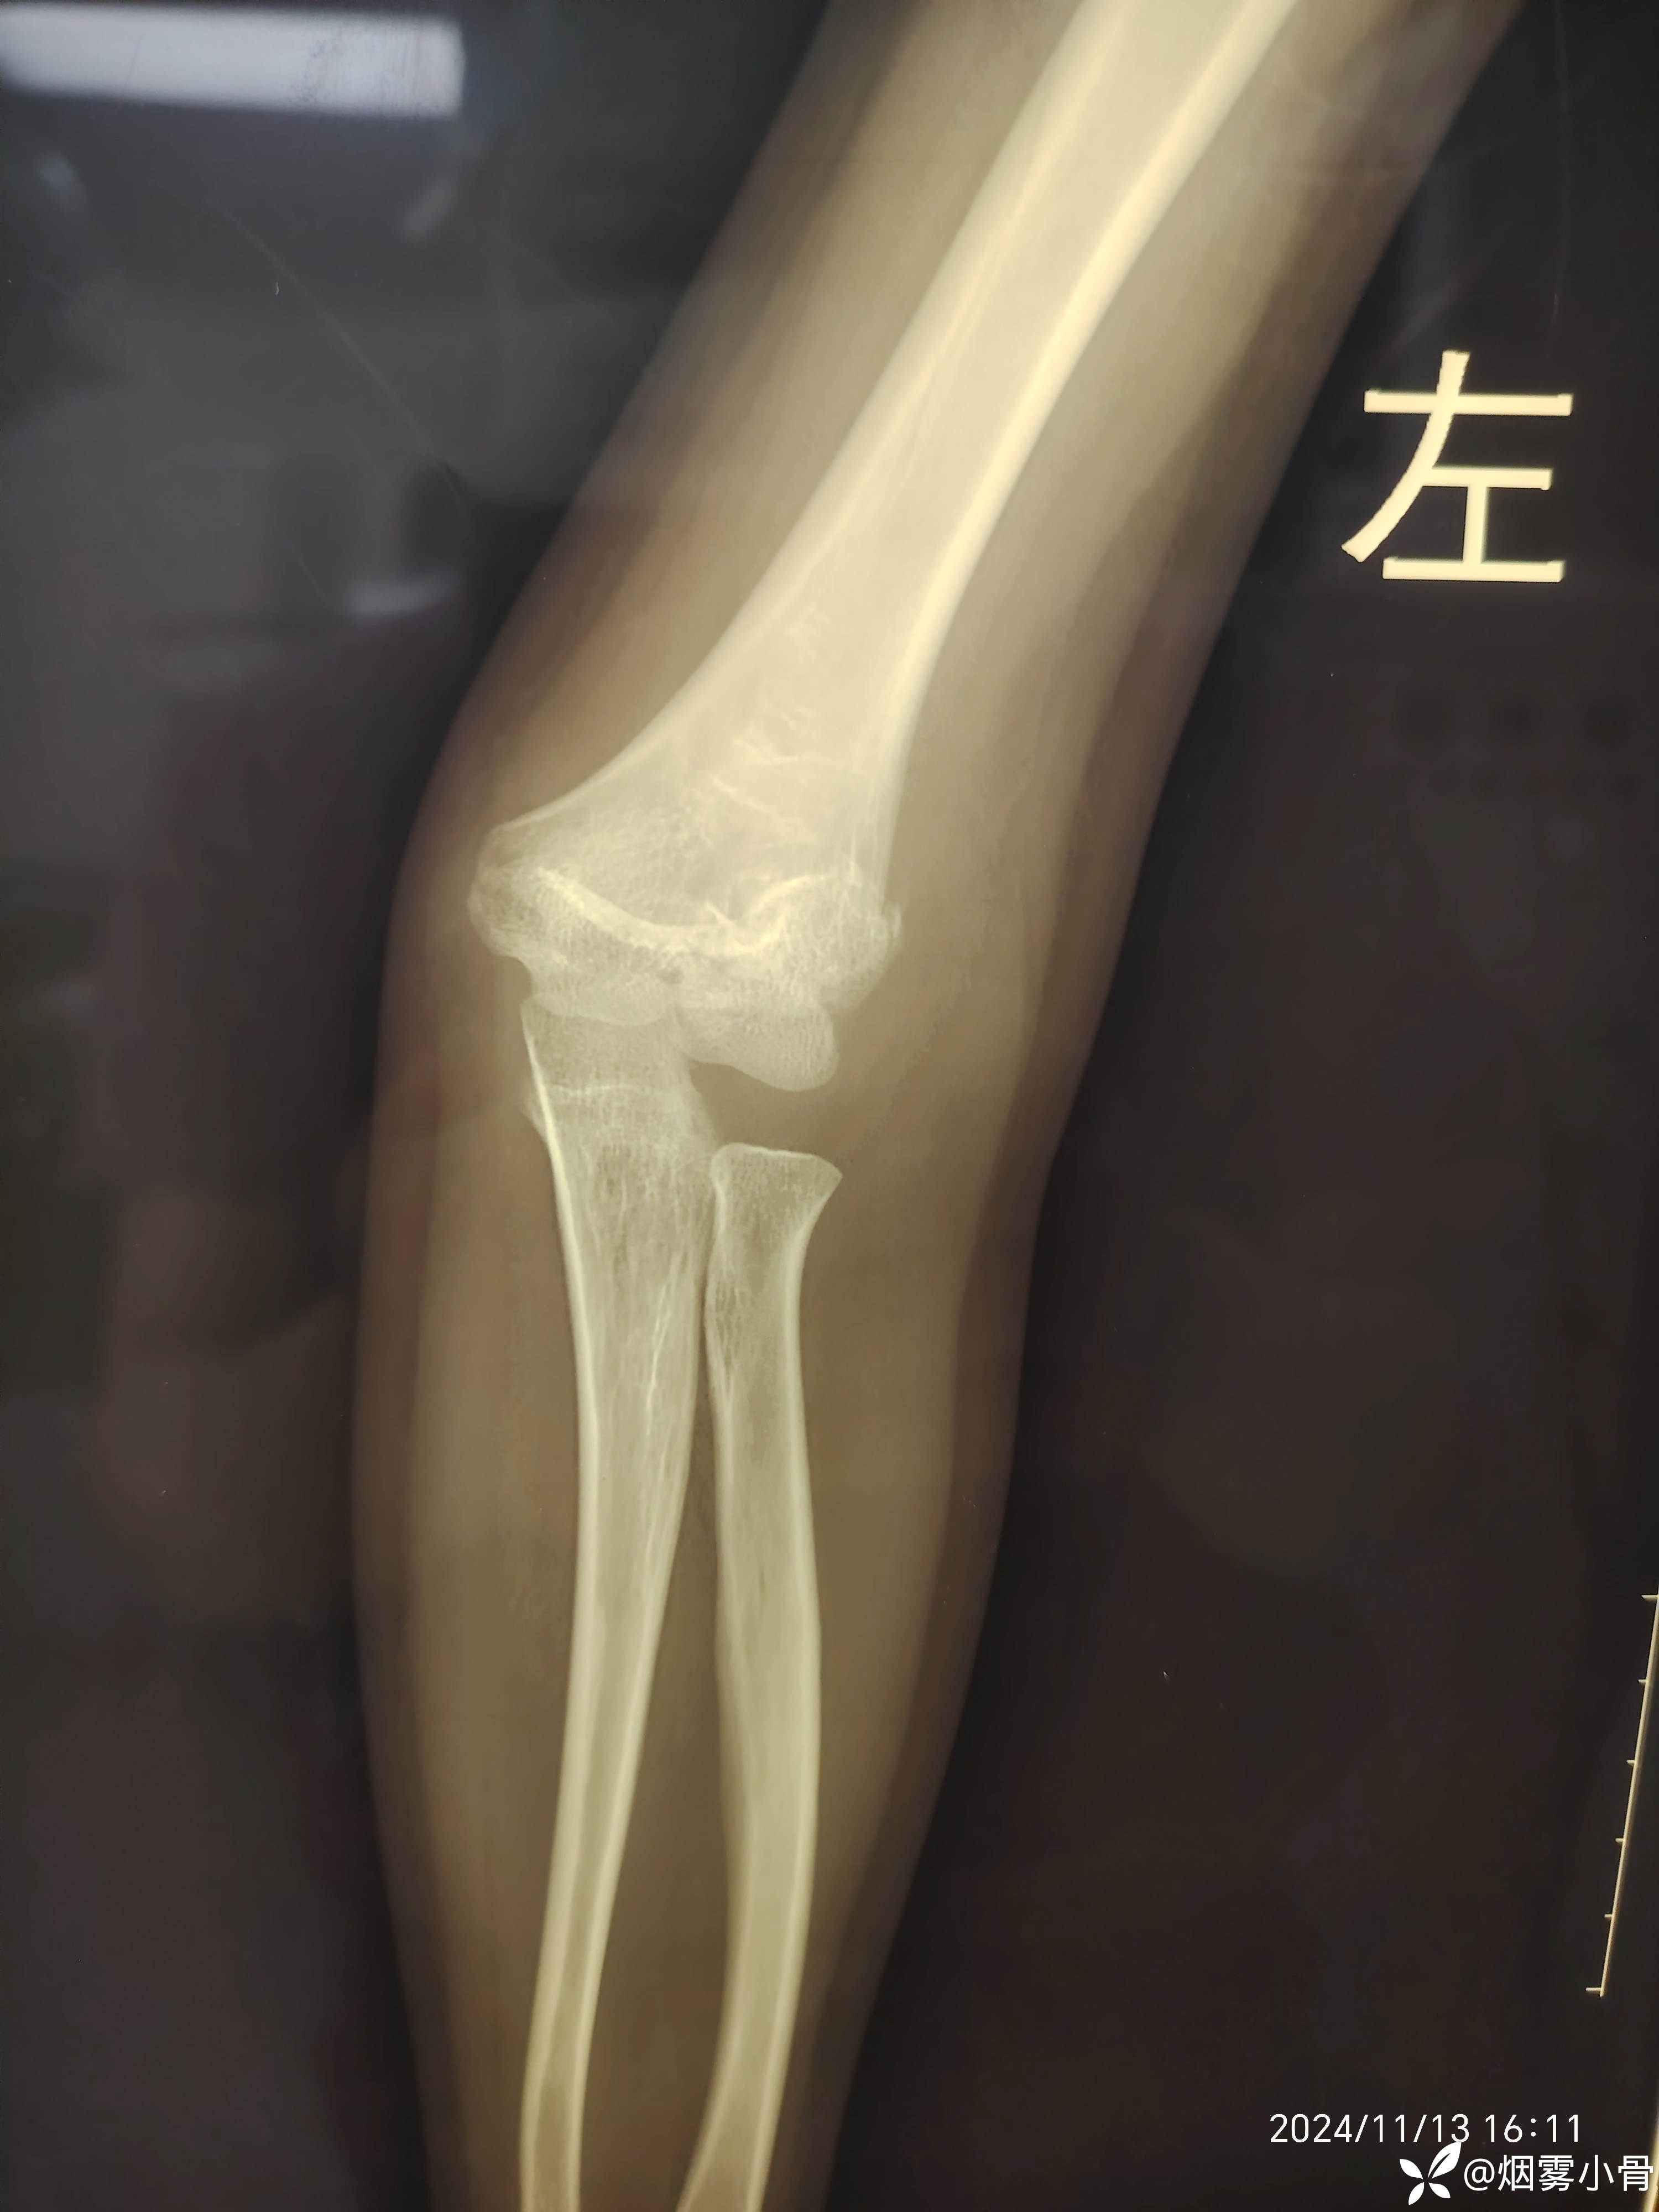

6岁肱骨髁上骨折,急诊30分钟完成零切开闭合复位克氏针内固定

【临床诊断】:左肱骨髁上骨折